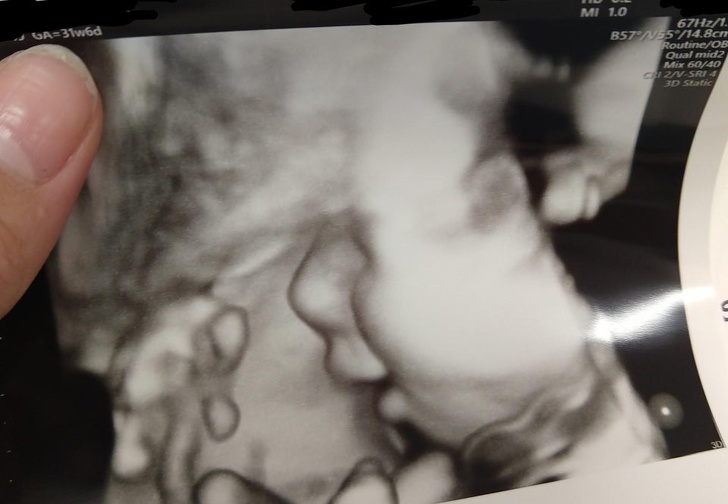

- The First Smile

This pregnant woman shared her ultrasound picture, where her unborn child can be seen smiling.